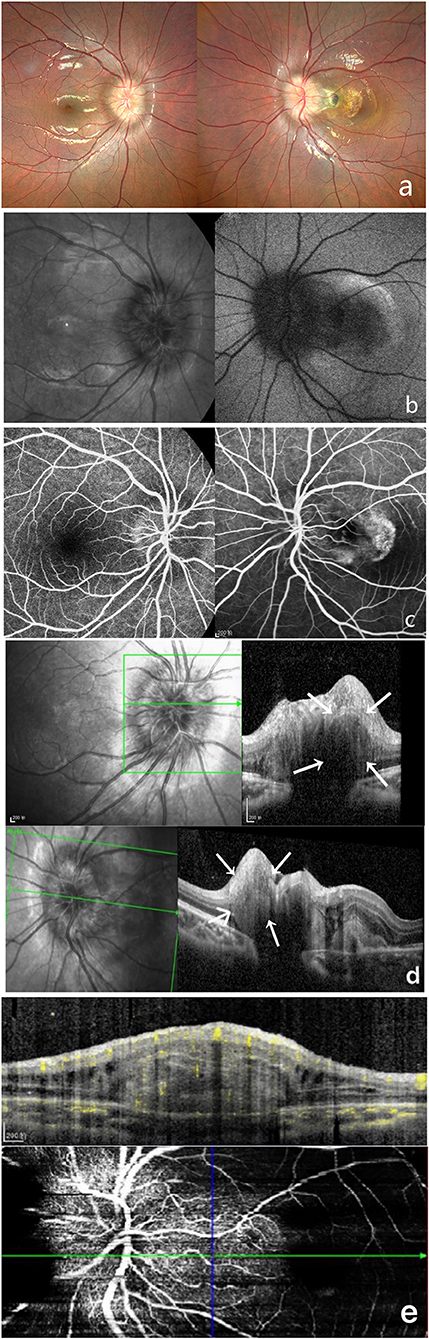

A 9-year-old girl was brought to our department by her mother complaining of reduced visual acuity in the left eye. LogMAR BCVA examination was 0 for the right eye and 0.5 for the left eye. Intraocular pressure and slit-lamp anterior segment examinations were normal. The initial diagnosis was binocular optic disc drusen (Figure 2).

Figure 2. Multi-modal image data of case 2. (a) Color fundus photography showed unclear optic disc boundaries, as well as are fibrosis and serous detachment of the retina in macular area. (b) This case did not show autofluorescence. (c) FFA shows a hyperreflective optic disc with poorly defined boundaries. (d) OCT shows a hyperreflective ovoid mass-like structure surrounded by a hyporeflective edge around the optic disc. (e) OCTA shows blood flow within this hyperreflective lesion.